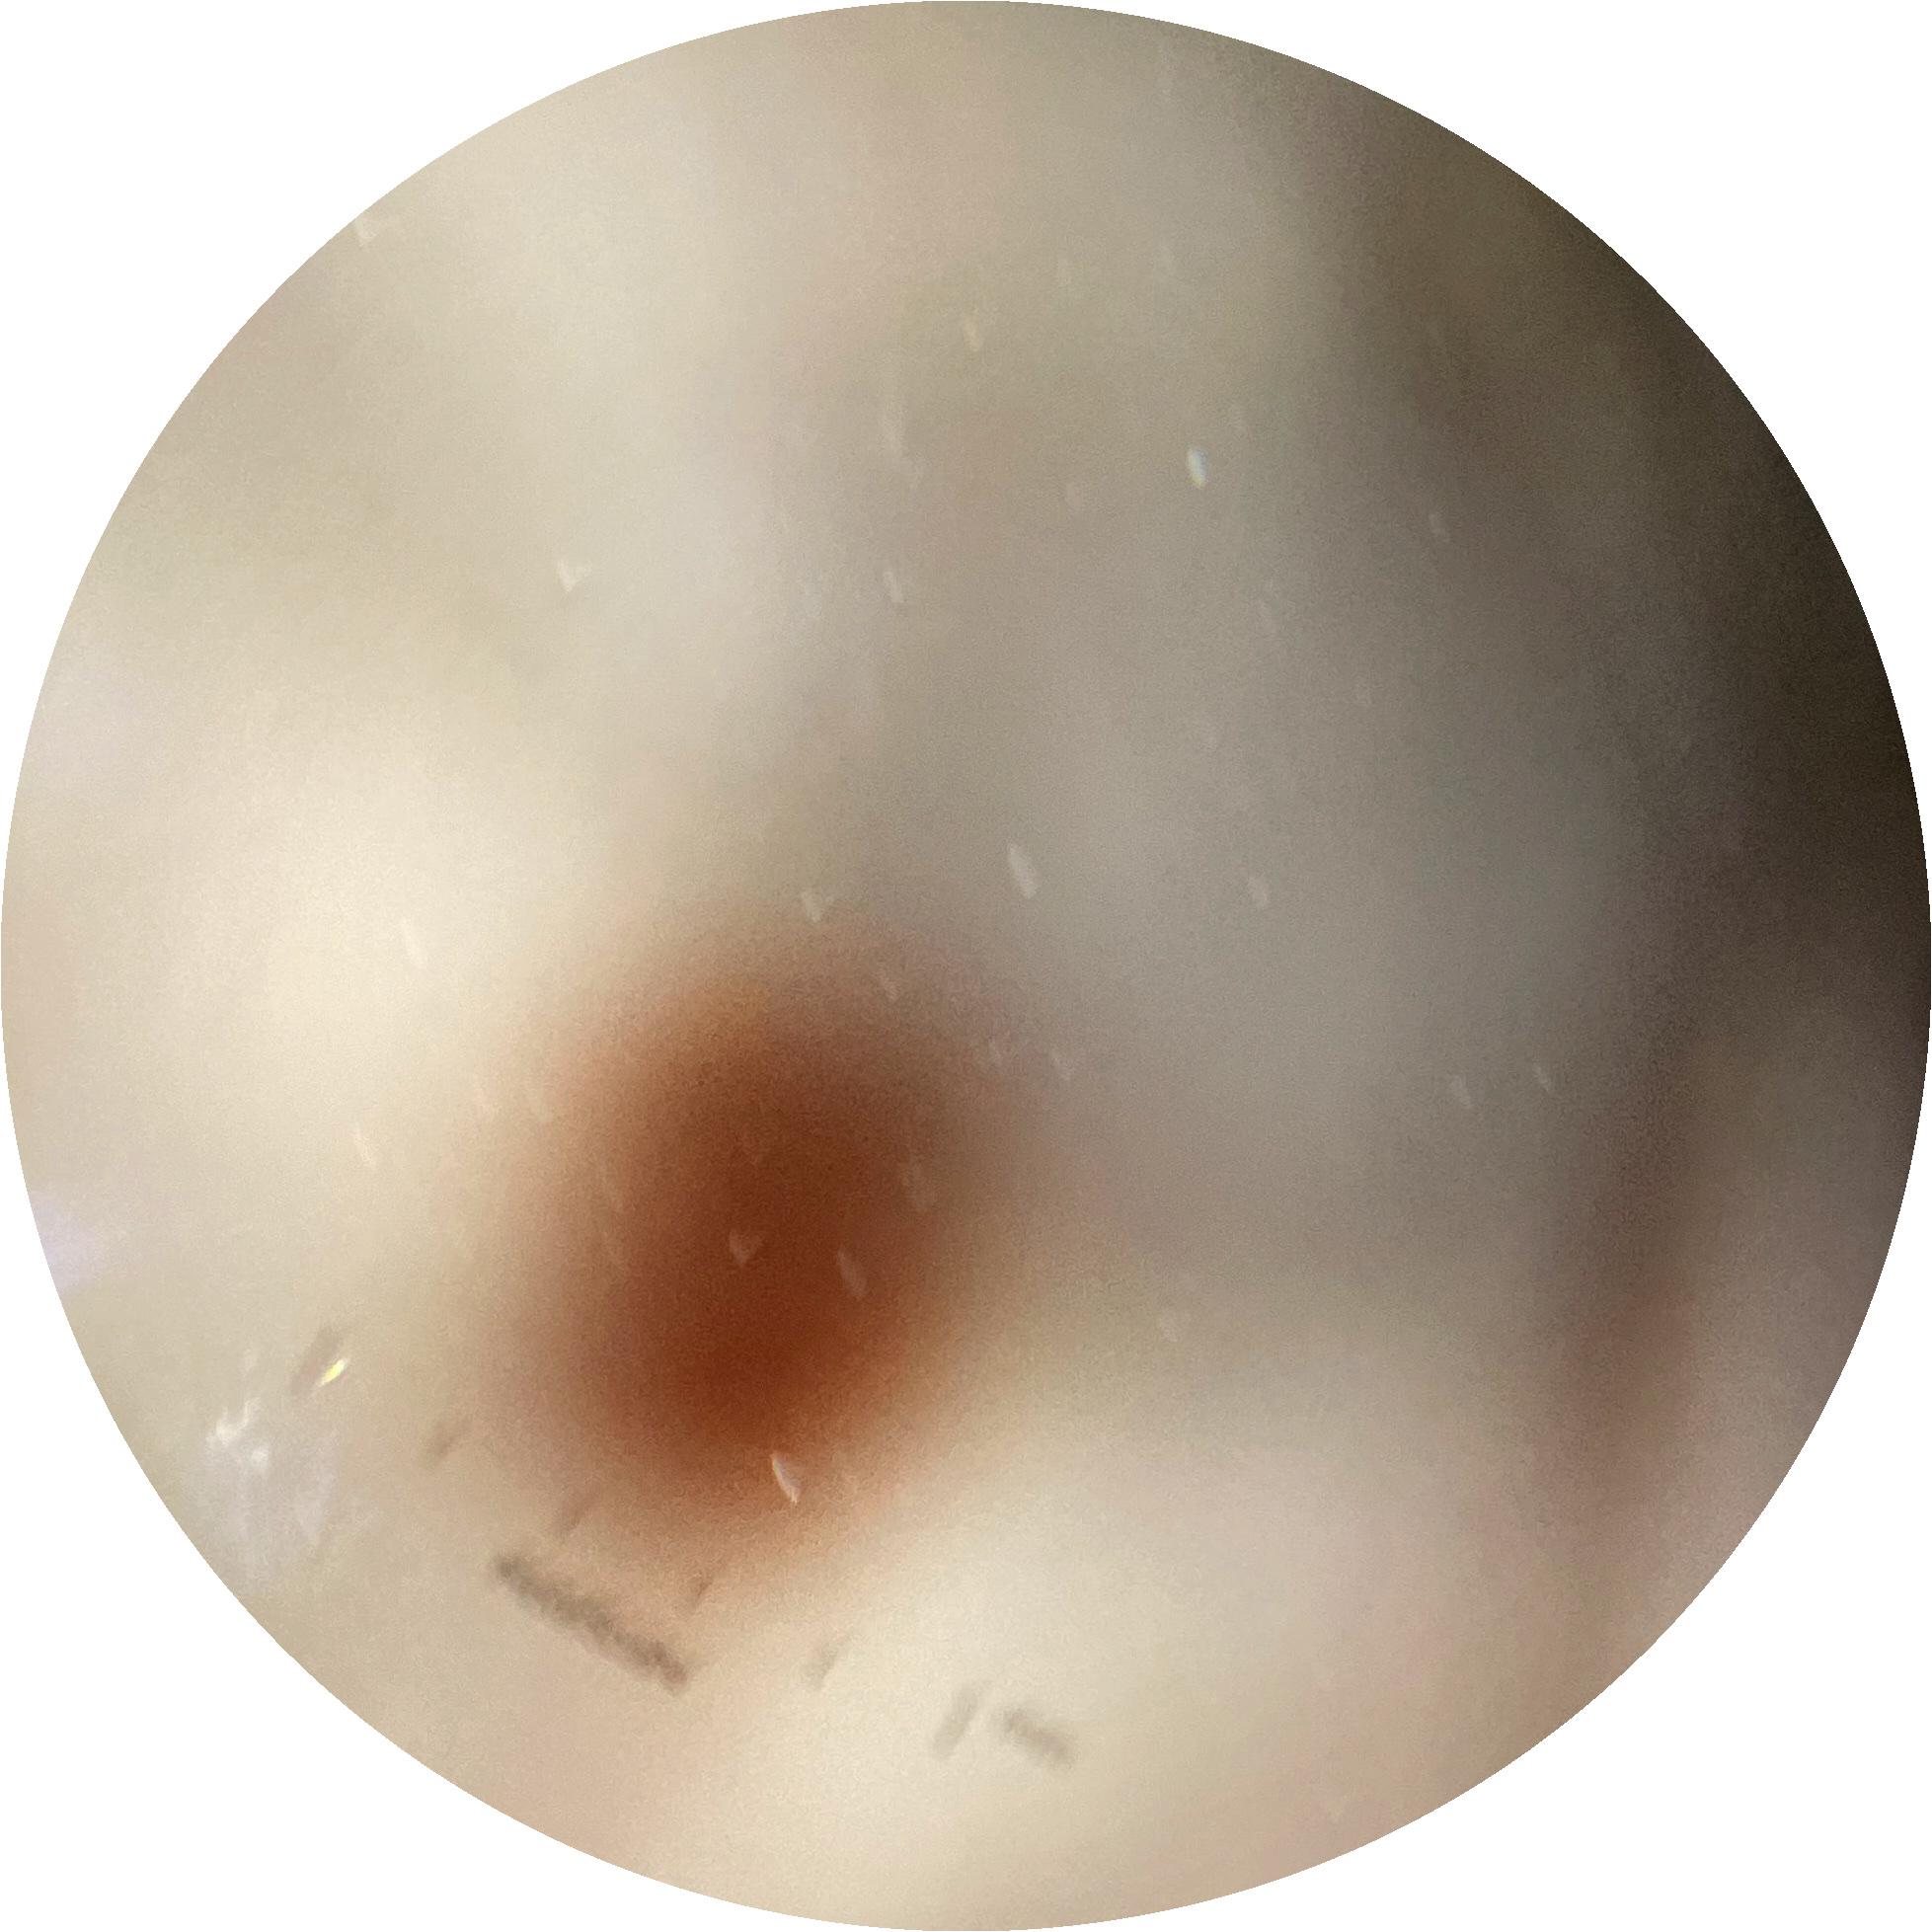

ISIC_8121870

image_type dermoscopic